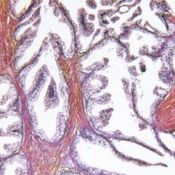

”Syövät lisääntyvät erityisesti yli 65-vuotiailla”

Syövät lisääntyvät erityisesti yli 65-vuotiailla, jotka varsinkin tarvitsevat tukea ja hoivaa, yhdistys kertoo.